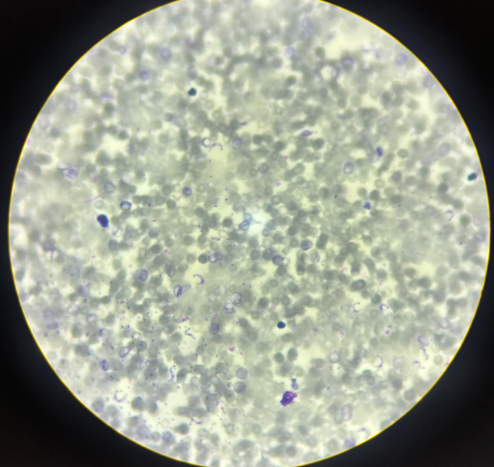

babesia sp stadia schizogonii krwinkowej

babesia sp stadia schizogonii krwinkowej